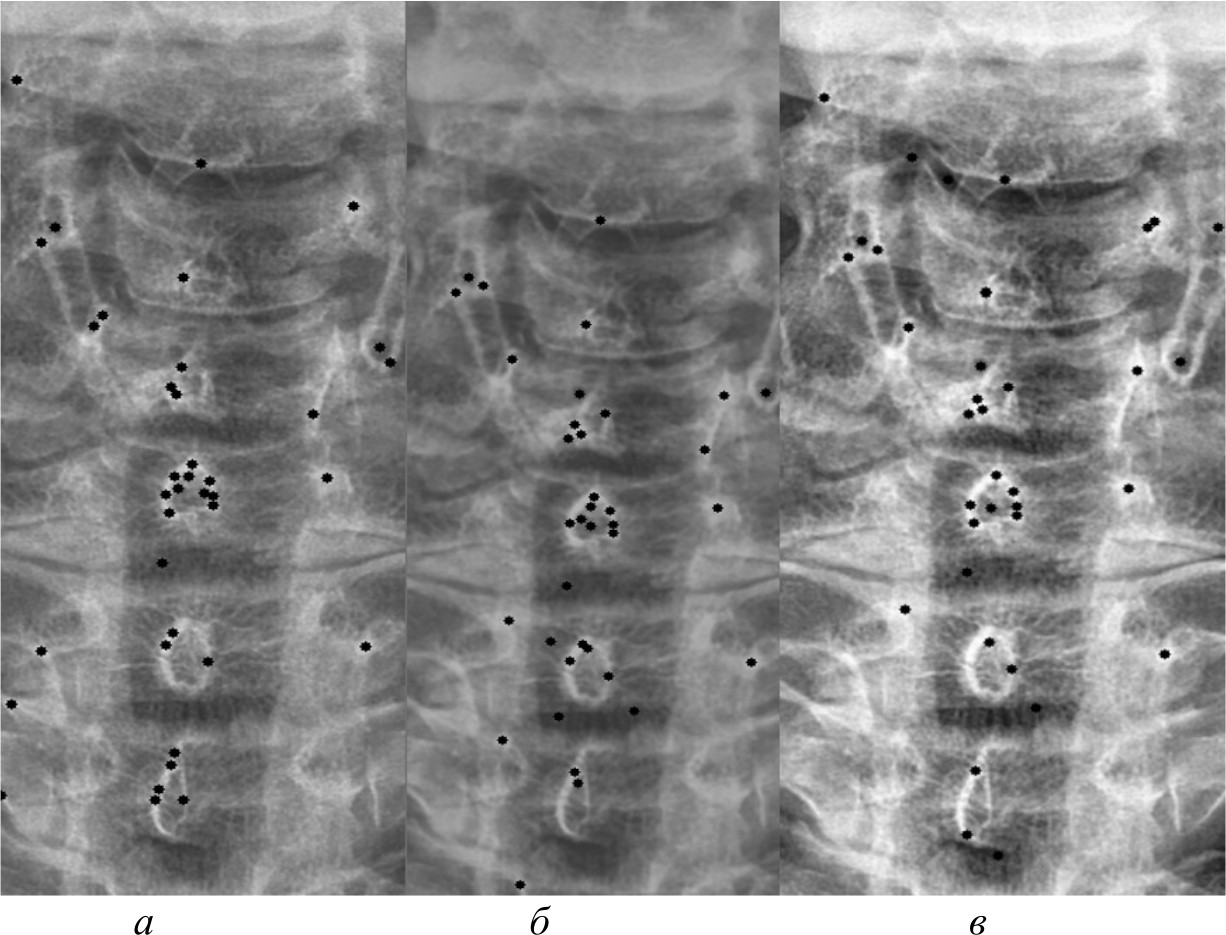

На рис. 4, 5 и 6 представлены результаты работы детектора Харриса, алгоритма Shi-Tomasi и SIFT при различных методах предварительной обработки изображений.

Рис. 4. Результаты работы детектора Harris на изображении, полученном при помощи специализированного программного обеспечения (а); результаты работы детектора Harris при методе адаптивной эквализации гистограммы (б); результаты работы детектора Harris при методе стандартной эквализации гистограммы (в); результаты работы детектора Harris при методе гамма-коррекции (г)

Рис. 5. Результаты работы алгоритма Shi-Tomasi на изображении, полученном при помощи специализированного программного обеспечения (а); результаты работы алгоритма Shi-Tomasi при методе базового отображения в Python (б); результаты работы алгоритма Shi-Tomasi при методе базового отображения Python с применением медианного фильтра (в); результаты работы алгоритма Shi-Tomasi при методе адаптивной эквализации гистограммы (г); результаты работы алгоритма Shi-Tomasi при методе стандартной эквализации гистограммы (д); результаты работы алгоритма Shi-Tomasi при методе гамма-коррекции (е)

Рис. 6. Результаты работы алгоритма SIFT на изображении, полученном при помощи специализированного программного обеспечения (а); результаты работы алгоритма SIFT при методе адаптивной эквализации гистограммы (б); результаты работы алгоритма SIFT при методе стандартной эквализации гистограммы (в)

После получения всех карт анатомических ориентиров составлена таблица и проведен сравнительный анализ. В таблице представлены данные сравнительного анализа методов предварительной обработки и алгоритмов распознавания анатомических ориентиров. В ней представлены следующие данные:

Метод | Принцип | Количество анатомических ориентиров (кластеров) и распределение по ним | Точность | Точность до обработки | ||

Harris | Shi-Tomasi | SIFT | ||||

Программа Dicom Image Viewer (эталон) | PNG-картинка полученная, специализированным программным обеспечением | 78 кластеров 6: 8, 15, 13, 14, 15, 13 | 80 кластеров 6: 8, 15, 15, 13, 14, 16 | 40 кластеров 4: 9, 15, 11, 6 | Harris – 87 %, Shi-Tomasi – 90 %, SIFT – 78 % | Harris – 65 %, Shi-Tomasi – 68 %, SIFT – 54 % |

Базовое отображение Python (Pillow) | Отображение при помощи библиотеки Pillow в Python | Не нашел | 80 Кластеров 6: 10, 10, 17, 15, 13, 15 | Не нашел | Shi-Tomasi – 45 % | Shi-Tomasi – 25 % |

Медианный фильтр | Отображение при помощи библиотеки Pillow в Python с применением фильтра Гаусса и медианного фильтра | Не нашел | 80 Кластеров 6: 8, 15, 11, 17, 14, 15 | Не нашел | Shi-Tomasi – 35 % | Shi-Tomasi – 22 % |

Адаптивная эквализация | Разбитие снимка на небольшие области и контрастирование каждой из них с применением фильтра Гаусса и медианного фильтра | 26 кластеров 6: 3, 1, 6, 4, 5, 7 | 80 кластеров 6: 4, 12, 17, 14, 12, 21 | 38 кластеров 6: 1, 4, 9, 10, 11, 3 | Harris – 77 %, Shi-Tomasi – 82 %, SIFT – 74 % | Harris – 65 %, Shi-Tomasi – 71 %, SIFT – 62 % |

Стандратная эквализация | Перераспределение значения пикселей для их равномерного распределения по диапазону. Данный метод выявляет более мелкие детали на изображении | 50 кластеров 6: 6, 8, 10, 8, 5, 10 | 80 кластеров 6: 8, 16, 16, 14, 10, 16 | 37 кластеров 6: 4, 8, 8, 9, 5, 3 | Harris – 91 %, Shi-Tomasi – 95 %, SIFT – 87 % | Harris – 74 %, Shi-Tomasi – 78 %, SIFT – 71 % |

Гамма-корректировка | Отображение при помощи библиотеки Pillow в Python с применением фильтра гамма-коррекции | 26 кластеров 6: 4, 2, 6, 4, 4, 6 | 80 Кластеров 6: 8, 15, 17, 12, 12, 16 | Не нашел | Harris – 55 %, Shi-Tomasi – 65 % | Harris – 38 %, Shi-Tomasi – 47 % |

Максимальное количество кластеров, которое может быть выделено, равно 6, так как на рентгеновских снимках выделялась часть спины, включающая 6 позвонков. Некоторые методы выделяют меньше кластеров, в то время как другие – больше; кроме того, часть методов не смогла распознать ключевые анатомические ориентиры вовсе. Это связано с особенностями алгоритмов и качеством предварительной обработки изображений.

На рис. 7 представлена гистограмма, на которой представлено количество ключевых анатомических ориентиров, распознанных при помощи трех алгоритмов на различных предварительно обработанных изображениях.

Рис. 7. Гистограмма сравнительного анализа методов предварительной обработки и алгоритмов распознавания ключевых анатомических ориентиров

Из данных таблицы видно, что наилучшим алгоритмом распознавания анатомических ориентиров является алгоритм Shi-Tomasi. Он распознал максимальное количество анатомических ориентиров вне зависимости от качества изображения, с которым работал, в то время как детектор Harris и алгоритм SIFT не смогли их распознать на изображениях, полученных при помощи базового отображения библиотекой Pillow, а также при применении медианного фильтра. Также алгоритм SIFT не смог найти ориентиры на изображении, полученном при гамма-коррекции.

Проанализировав все методы предварительной обработки и то, как алгоритмы смогли распознать ключевые анатомические ориентиры на них, можно сделать несколько выводов. Наилучшим методом оказалась стандартная эквализация изображений, при которой алгоритм Shi-Tomasi распознавал анатомические ориентиры с точностью около 95 %. Использование специализированного программного обеспечения также показало неплохие результаты, но немного уступало стандартной эквализации по точности распознавания – около 90 %. Остальные методы, такие как применение фильтров или гамма-коррекция, показали более низкую точность, в диапазоне от 35 до 75 %. В свою очередь, применение любого метода предварительной обработки повышало точность распознавания ключевых анатомических ориентиров на 15–25 %. В итоге наиболее предпочтительными методами оказались стандартная эквализация и специализированное программное обеспечение.